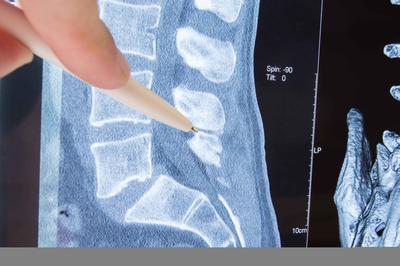

3. 腰间盘突出

腰椎间盘突出压迫右神经根后,患者容易发生右腿疼痛。如果严重的话,还会伴有右腿外侧和右脚后部麻木。可以通过腰椎磁共振检查进行诊断分析,若疼痛严重需要注意休息,并减少活动量。